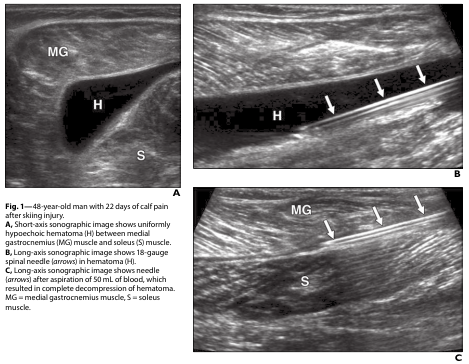

실제로 12~15세 소년 4명을 대상으로

외상 후 10일 이내에 바늘을 이용해

고인 피를 뽑아냈더니,

시술 즉시 안구 운동 기능이 회복되고

안구 돌출이 사라졌습니다.

즉, 혈액이 응고되기 전

조기에 처치하는 것이

회복 기간을 획기적으로 줄이는

핵심이라는 사실이 입증된 거죠.